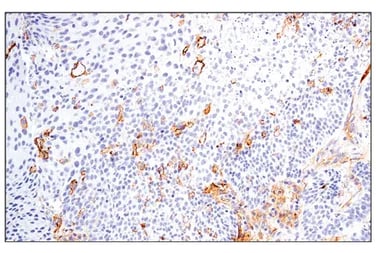

Successful metastasis to a new organ also requires tumor cells to exit the vasculature at specific “hot spots” of extravasation, where local endothelial activation and junction remodeling create sites for tumor escape into the surrounding tissue. These hot spots can be initiated both by local inflammatory cytokines and by tumor‑derived factors and extracellular vesicles that are delivered to distant organs, where they activate endothelial cells, increase vascular permeability, and help pre‑establish a permissive premetastatic niche. At these sites, tumor and monocyte-derived cytokines and chemokines promote endothelial activation and retraction, partly via E‑selectin upregulation, enabling transient adhesion of circulating tumor cells to the vessel wall.

Following this, stable adhesion is established through interactions between tumor cell integrins and adhesion molecules such as ICAM-1 (CD54) and ALCAM on endothelial cells, together with endothelial receptors including ICAM-1, VCAM-1, and lamin-rich basement membrane components that anchor adherent tumor cells to the vessel wall. Next, tumor-derived VEGF-A activates VEGFR signaling in endothelial cells. Downstream, FAK/Src signaling promotes VE‑cadherin phosphorylation and causes dissociation between VE‑cadherin and β‑catenin complexes at adherens junctions, leading to junction destabilization and opening paracellular routes for tumor extravasation.

![]() |

| IHC analysis of paraffin-embedded human urothelial carcinoma using CD54/ICAM-1 (E3Q9N) Rabbit Monoclonal Antibody #67836 performed on the Leica BOND RX. | IHC analysis of paraffin-embedded CT26.WT syngeneic tumor using VE-Cadherin (F4K3Y) Rabbit Monoclonal Antibody #60787. |

Together with local stromal and immune cells, these extravasation hot spots act as vascular exit points that disseminated tumor cells exploit to leave the circulation and begin colonizing distant tissues.